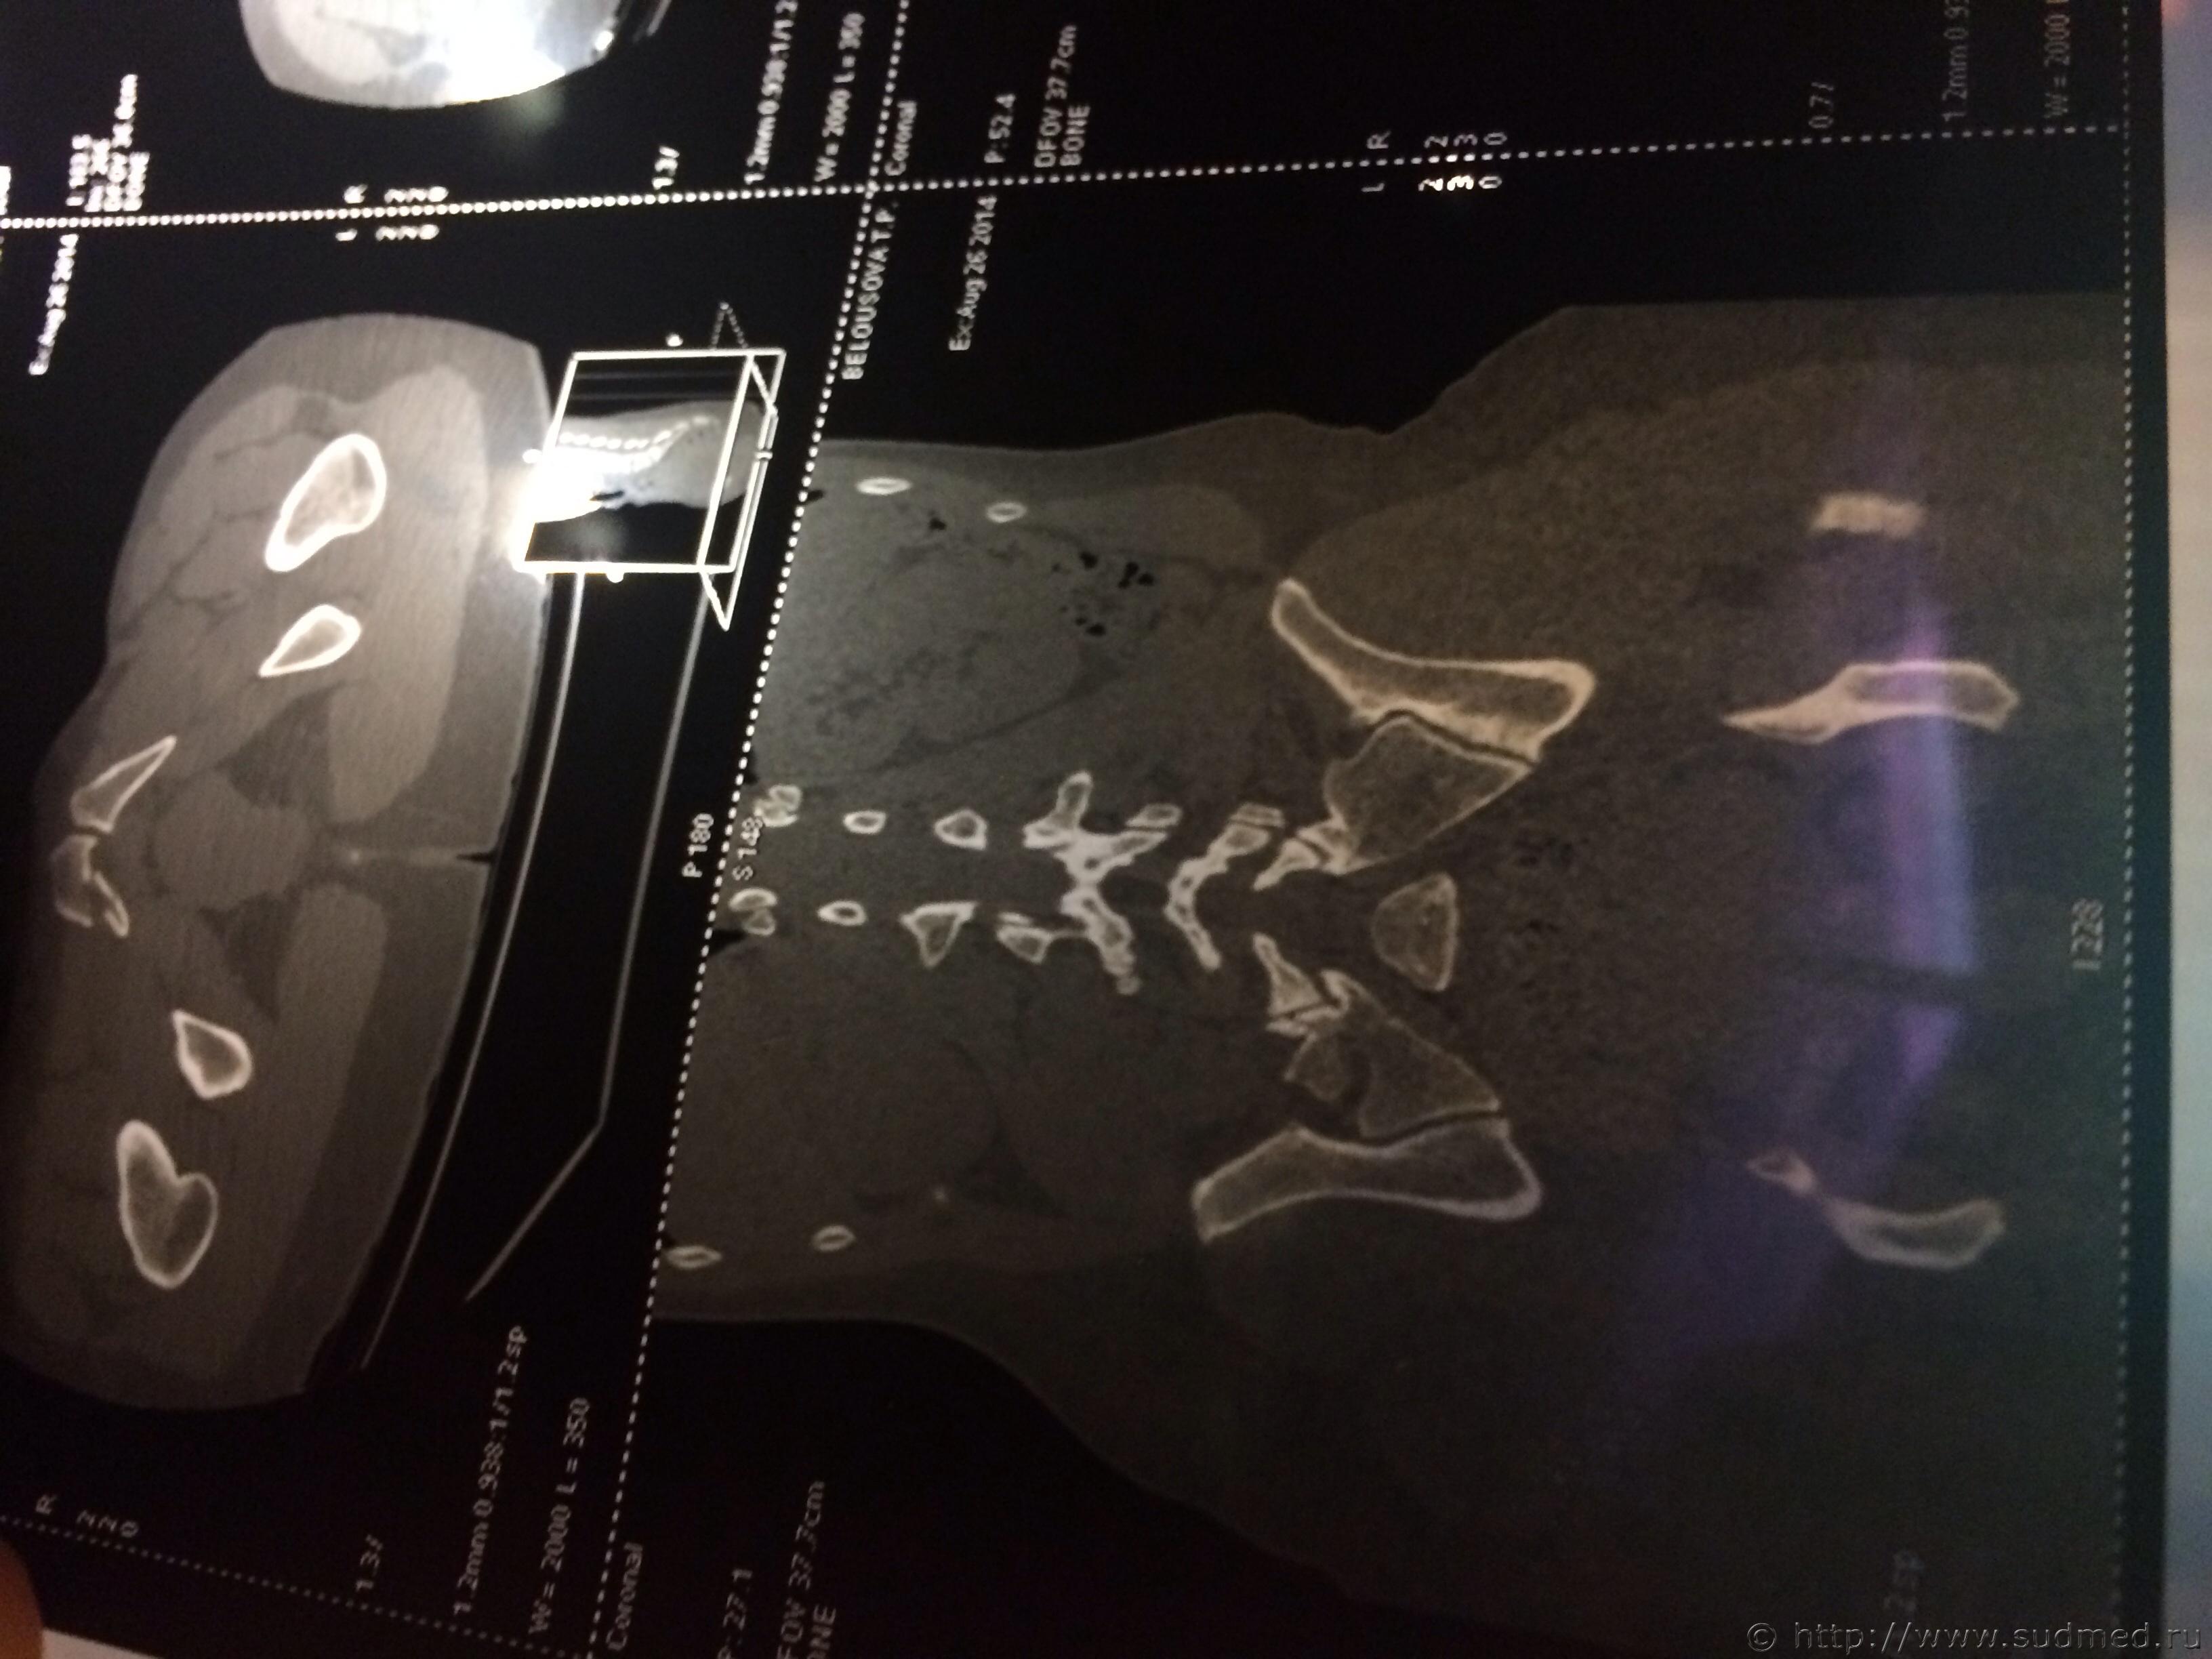

Спасибо! У меня результаты КТ, ошиблась)

КТ

Как мне видится - вертикальный перелом крестца. Тяжкий вред.

Впрочем, оставляю небольшую вероятность, что я не видел все сканы, да и качество их здесь, разумеется, хуже, чем изображение на пленке или на экране компьютера у врача, работающего на томографе.